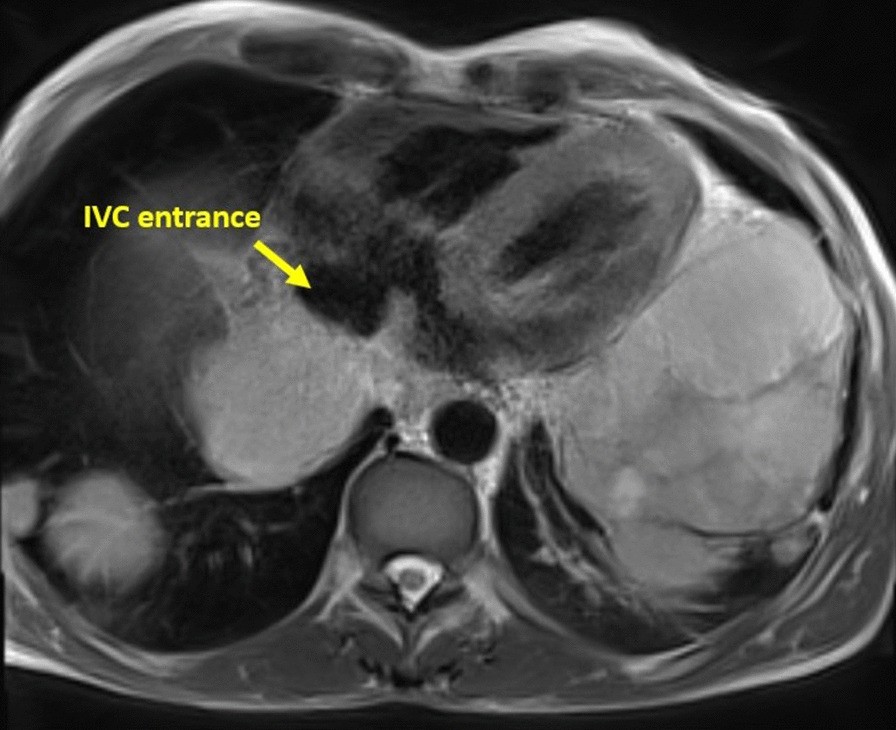

Fig. 15

From: Society for Cardiovascular Magnetic Resonance 2019 Case of the Week series

Case 4. Axial T2 fat suppression image. Pericardial infiltration over the atria, yet, no effusion and no atrial extension. The inferior vena cava (IVC) entrance to the right atrium is spared